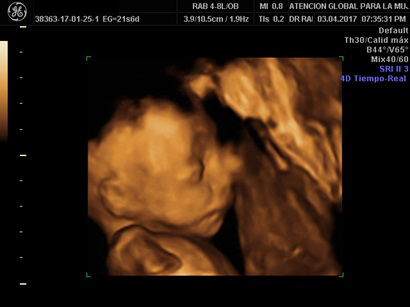

• Ultrasonido de Crecimiento

Se realiza entre las semanas 18 a 23.6 semanas de gestación

• Se evalúa Crecimiento Fetal (realizar uno entre las 28 a 32 semanas y el último a las 37 semanas).

• Aún se puede detectar algunas enfermedades

• Este ultrasonido valora además placenta, líquido amniótico y cordón umbilical.

• Perfil Biofísico

Se evalúan el Índice de líquido amniótico, movimiento fetal, el tono muscular, la postura del feto y la hemodinamia fetal (DOPPLER) (Flujos sanguíneos)